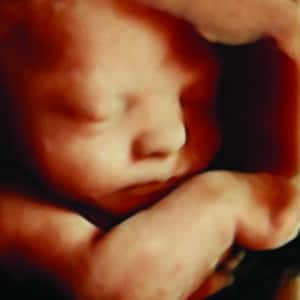

Explore our Photo Gallery and see the real results from Knit 4D Ultrasound. Every image you see  from 2D, 3D, 4D, to HD live ultrasounds  was captured by our highly trained team using our state-of-the-art ultrasound machine. We can begin creating amazing 3D/4D keepsake images as early as 8 weeks, giving you a beautiful first look at your baby.